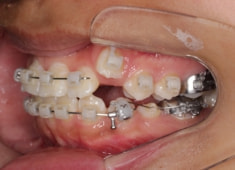

治療開始から5ヶ月後